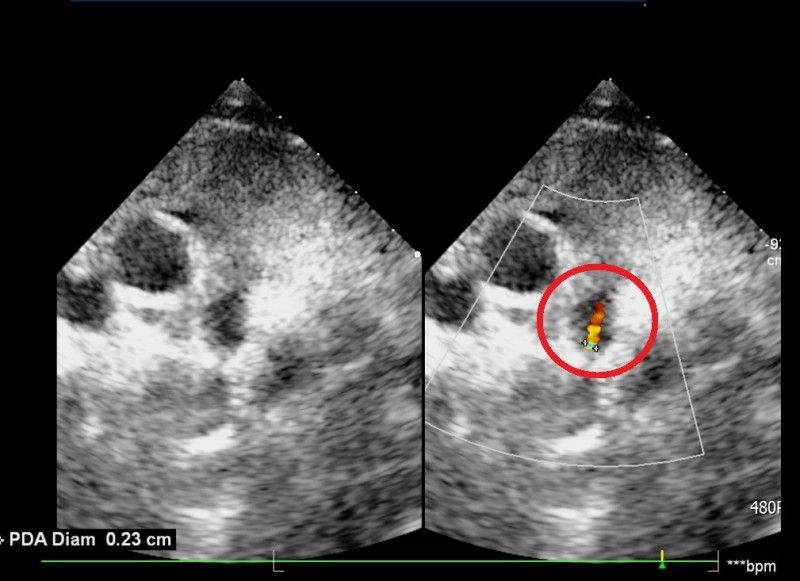

〔記者彭健禮/苗栗報導〕苗栗1名7歲女童因B型流感到大千綜合醫院急診就醫。醫師擔心引發心肌炎,安排住院觀察,經心臟超音波檢查,竟發現女童患有「開放性動脈導管(PDA)」。經大千小兒心臟科醫師詹裕仁與台中榮民總醫院總院長傅雲慶聯手,完成苗栗縣首例「兒童心導管微創關閉手術」,術後女童鼠蹊部傷口僅0.2公分,隔天即出院。

詹裕仁指出,「動脈導管」原本是胎兒時期主動脈與肺動脈間的一條重要交通管道。一般而言,嬰兒出生後開始自主呼吸,這條導管應在數天內自動閉合;若導管持續未關閉,便稱為「開放性動脈導管」,這會導致主動脈的高壓力血液分流至肺動脈,造成肺部血流量過多,增加心臟負擔。

詹裕仁進一步說明,早期心臟修補需透過傳統開胸手術,傷口大且復原期長。現今「心導管關閉手術」已成為主流,手術經由鼠蹊部的小傷口,將導管送入心臟。在X光導引下,將特殊的「鎳鈦合金封堵器」放置在缺損處,阻斷異常血流。此項手術的優點為:傷口極小(僅約0.2公分)、免插管、免開刀、出血量少、術後恢復極快。